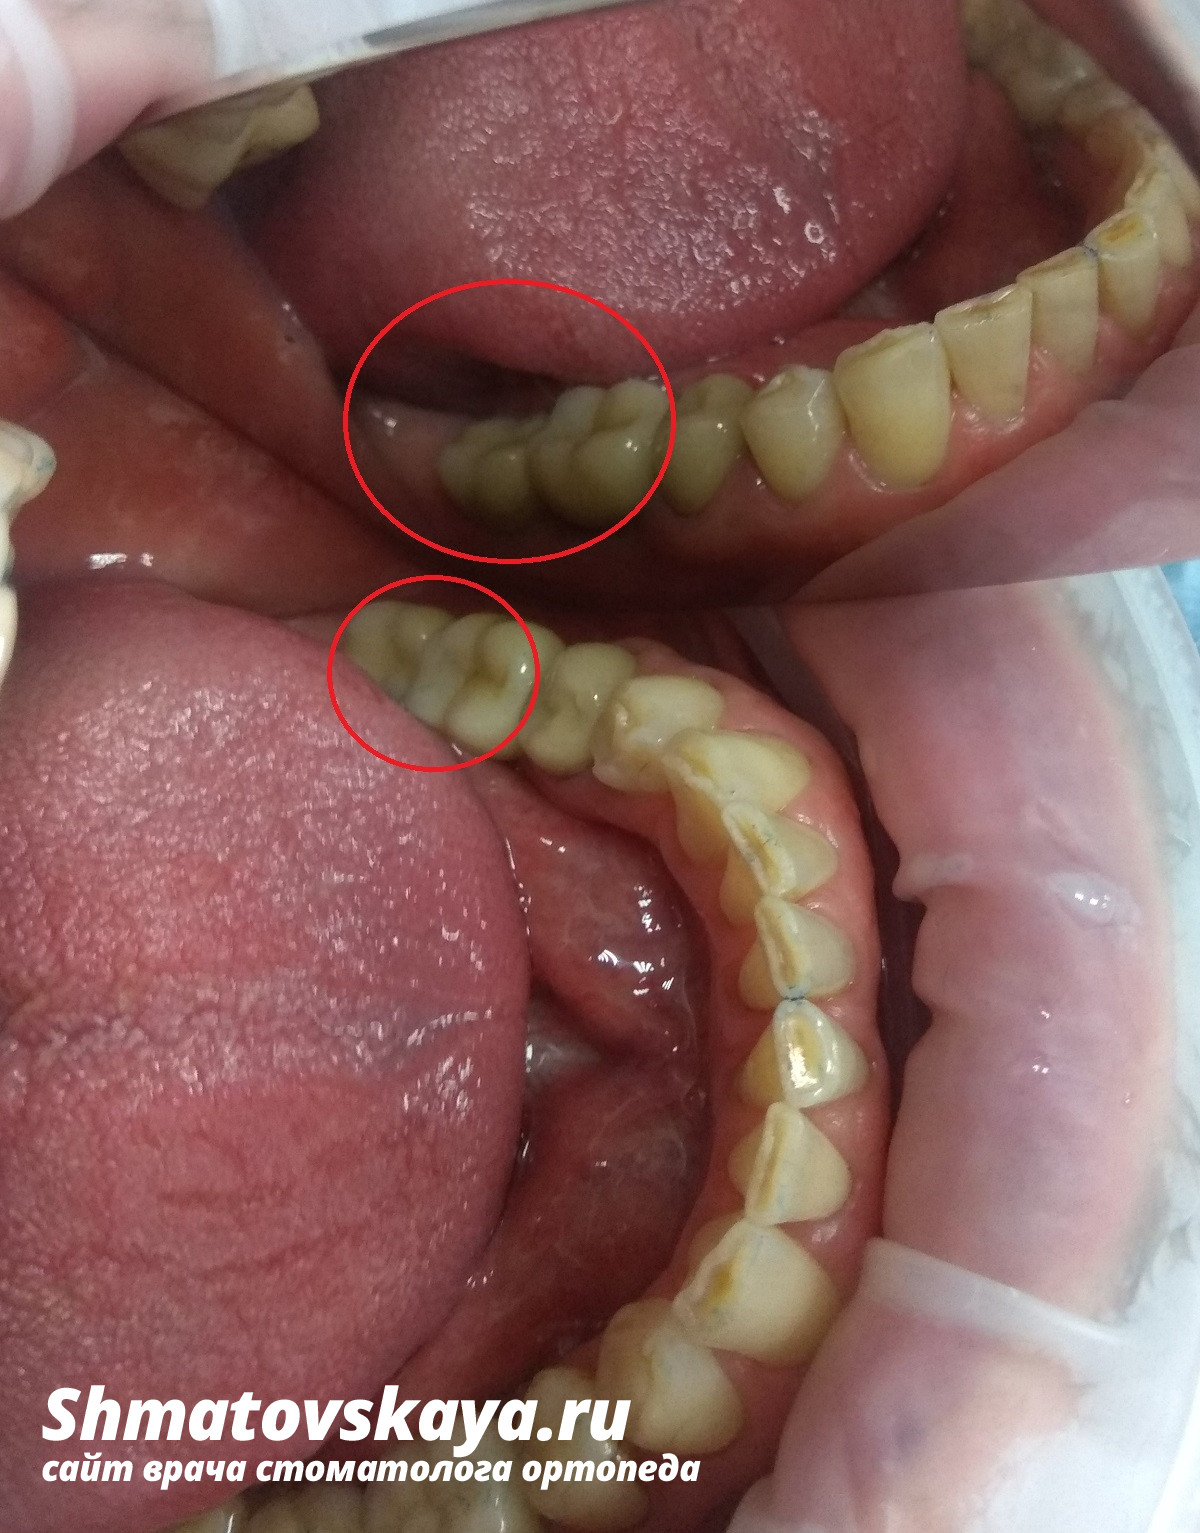

Пациент М. обратился в стоматологическую клинику с целью протезирования отсутствующих жевательных зубов на нижней челюсти.

В данной клинической ситуации отсутствуют зубы в боковом отделе зубного ряда нижней челюсти. Это не позволяет полноценно пережёвывать пищу и нарушает естественное распределение нагрузки и в дальнейшем может привести к разрушению и потере других зубов.

1. Установить имплантаты (система Osstem) в область отсутствующих 36, 37 зубов.

2. Установить металлокерамические коронки с винтовой фиксацией с опорой на имплантаты в область 36, 37 зубов.